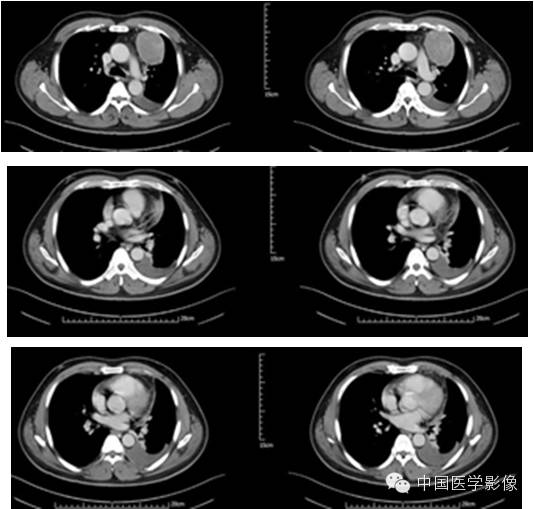

病例2【病史】

患者男,47岁。

患者因“查体发现右纵膈区占位2周”入院。患者无胸痛、胸闷,无发热、盗汗,无咳嗽、咳痰。CT示:右心膈角处新生物,考虑来自叶间裂的炎性假瘤可能性大,不除外其他肿瘤可能。

专科查体:(-)

入院诊断:右下纵膈占位:心包囊肿?炎性假瘤?

【影像资料】

平扫

动脉期

静脉期

延迟期

【病理结果】

孤立性纤维性肿瘤